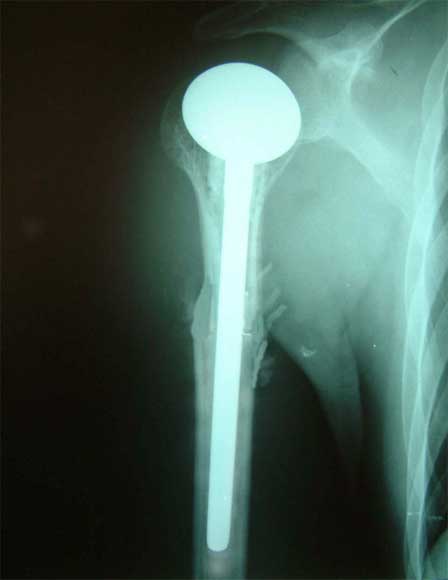

肱骨骨折,3次钢板和钢丝固定后失败。改用带锁髓内钉固定,4个月后骨折愈合。